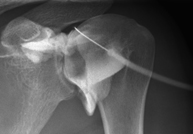

- X-ray arthrography

This X-ray based procedure involves injecting a contrast agent into the joint to detect lesions in certain structures (cartilage, bone, tendons, etc.) by observing the distribution of the contrast agent.

- Pelvis X-ray

This procedure uses X-ray imaging to examine the pelvis, especially the pelvic bones.